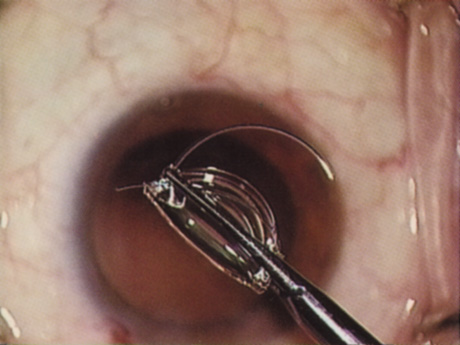

COMPROMISED ZONULES

The introduction of innovative adjunctive devices was able to improve the management of challenging cases. The capsular tension ring introduced independently by Tsutomu Hara37 and Toshiyuki Nagamoto38 in Japan was identified as a major weapon in managing zonular weakness by Ulrich Legler and Bernd Witschel of Germany.39 The CTR came to the United States in 1993,40 after which modifications by Robert Cionni,41 Iqbalk Ahmed and Alan Crandall,42 and Burkhard Dick were developed. Iris reconstruction had been primarily limited to suture techniques developed by Malcolm McCannel43 and later Steven Siepser.44 The prosthetic irides were introduced by German surgeons, Ranier Sundmacher45 and Volker Rasch,46 and brought to the United States by Kenneth Rosenthal and then Robert Osher in 1996.47 Although many devices had been developed to mechanically open the small pupil, it was the stretch technique developed by Luther Fry that greatly simplified these difficult cases.48 Improving visibility by staining the anterior capsule of the white cataract was introduced by Masayuki Horiguchi from Japan (ICG)49 and Gerritt RJ Melles from The Netherlands (Trypan Blue).50